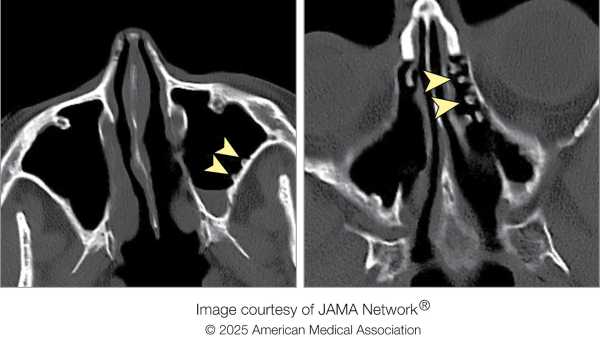

Полоскання холодною водою залишило у жінки нарости у вигляді бруківки в пазухах носа